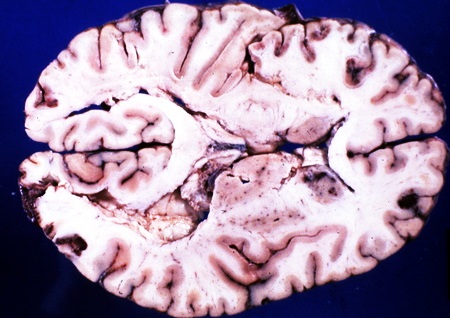

- На нейросонографии – эхогенность паренхимы мозга диффузно повышена, боковые желудочки сужены. Позже у грудничка формируются перивентрикулярные кистозные полости, и развивается атрофия тканей больших полушарий мозга (у недоношенных детей процент формирования этих патологий гораздо выше).

- На компьютерной томограмме – очаговое снижение плотности паренхимы, ликворные пространства значительно сужены.

- МРТ – выраженные паренхиматозные поражения.

Изменения, формирующиеся в ЦНС при церебральной гипоксии тяжелой степени течения, часто приводят к необратимым последствиям. Родителям такого малыша необходимо начать лечение как можно раньше, еще в первые часы жизни ребенка, для того чтобы снизить риск развития серьезных осложнений.